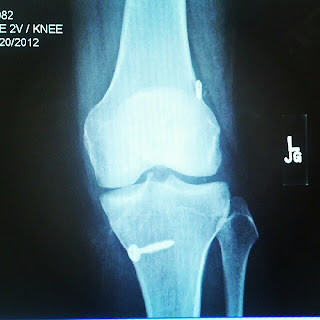

It's been 6 months and 13 days (or 197 days) since my surgery. This means I have just passed the halfway point of my recovery. I've had ups and downs (but no turns! hahaha) since my last post. I graduated from physical therapy, I've had a few follow ups with the doctor, and I have gone back to all my dance classes.The doctor says everything is on track-- no leaps or turns, but for the most part I can work out and dance as I feel comfortable. I'm teaching 2 jazz classes, 2 hip hop classes, and 2 tap classes a week. I've taken it slow, but try to do a little more each week. my scare is still not very attractive, but hopefully it will chillax as time goes by. My hip bursitis that I developed as a result of my surgery has stayed longer than it was welcome-- which was not at all. I got a cortisone shot in September, it helped for about a month and a half, and then the pain came creeping back. If I have dance, the next morning I walk with a limp. If I sit for too long, when I get up, I walk with a limp. 50 cent was hit with a few shells but doesn't walk with a limp. I get hit with a scalpel and now I do walk with a limp. Figures. Ghetto Fab.

Dr. A says the bext 6 months are tough because I will think I am better than I am. I will get frustrated that I can't do things. I will be pissed that progress is slow and at times be unnoticeable. I need to be extra careful because it is still fragile and healing. He says his best advice is... patience. Great... cause everyone knows I am super great at being patient. I will see him again right around the 1 year mark. Hopefully I will be back to normal by then.